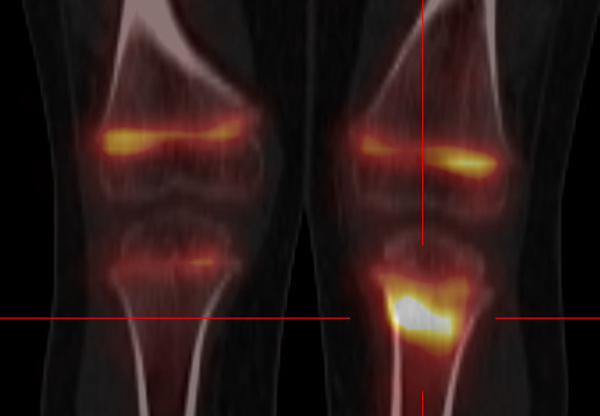

-Douleur osseuse chez un patient aux antécédents de néoplasie -Augmentation des marqueurs tumoraux chez un patient suivi pour néoplasie -Guide pour biopsie ou exérèse -Guide pour une infiltration...